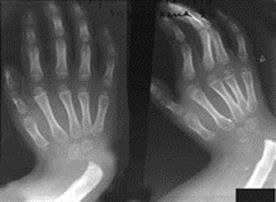

Лучевая косорукость. Эта аномалия развивается при отсутствии лучевой кости.

Рис.5. Рентгенограмма ребенка с лучевой косорукостью.

Дефект может быть двусторонним. Одновременно недоразвиты мышцы предплечья с лучевой стороны, первый палец кисти, кости запястья. Кисть наклонена в сторону лучевой кости (вовнутрь), функция ее резко нарушена, а в связи с отсутствием первого пальца кисти невозможен захват предметов. Лечение врожденной косорукости включает много этапов. Уже сразу после рождения ребенка назначают массаж, лечебную физкультуру. Для исправления контрактуры суставов накладываются гипсовые повязки. Первая операция выполняется в возрасте 2 лет. Потом могут понадобиться дополнительные оперативные вмешательства.